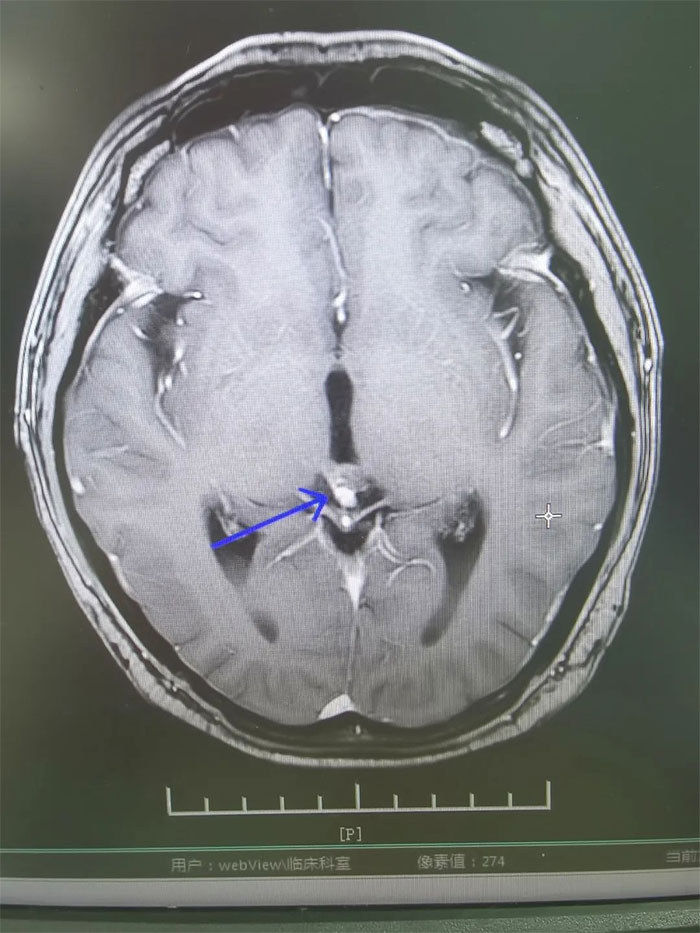

▲ 放療后復(fù)查,病灶明顯縮小

經(jīng)過一個完整療程的放療,患者沒有出現(xiàn)明顯并發(fā)癥,頭痛、惡心嘔吐癥狀得到緩解。復(fù)查MRI,影像顯示病灶明顯縮小,梗阻性腦積水消失。進一步完善檢查評估后,小剛已順利出院。眼見短時間內(nèi)病情即得到控制,小剛對生活又重拾信心,表示一定會以積極的心態(tài)面對人生。